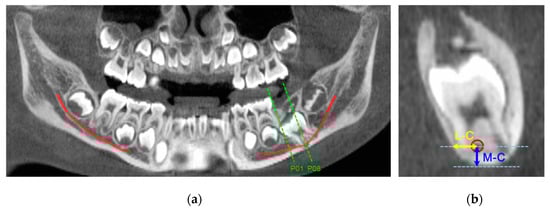

| Variable | n | Mean ± SD (mm) | Minimum (mm) | Maximum (mm) | p-Value | |

| M–C 1 | ED 3 | 42 | 4.86 ± 1.07 | 3.01 | 7.15 | 0.000 * |

| Normal | 42 | 6.50 ± 1.06 | 3.98 | 8.78 | ||

| L–C 2 | ED 3 | 42 | 2.74 ± 0.74 | 1.54 | 4.27 | 0.027 * |

| Normal | 42 | 3.09 ± 0.71 | 2.01 | 5.03 | ||